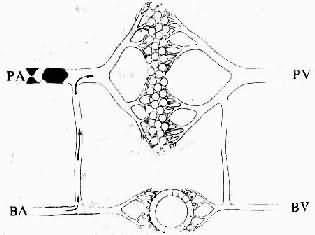

图3-13 肺动脉栓塞时的血流变化示意图

PA:肺动脉;PV:肺静脉;BA:支气管动脉;BV;支气管静脉(仿Eder)

需指出的是,肺梗死发生的先决条件为事先需有肺淤血的存在。这是因为肺有肺动脉和支气管动脉双重血液供应,两者之间有丰富的吻合支,有肺循环正常的条件下,肺动脉分支栓塞不会引起梗死,因为支气管动脉可借助吻合支供血于该区肺组织(图3-13);但如肺原先已有淤血,致肺静脉压增高,当肺动脉分支栓塞时,单纯以支气管动脉的压力不足以克服局部范围内的肺静脉阻力,局部肺组织乃发生梗死。这便是肺梗死常见于二尖瓣疾患而且是出血性的原因。